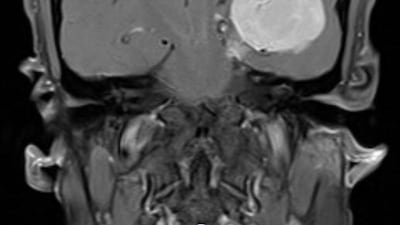

It was only when he booked himself in for an MRI scan that the giant tumour, which had developed its own blood supply, was discovered.

The tumour was at the base of the skull and pushing into the brain, which made the operation complicated.

But it was carried out successfully with the help of "neuro-navigation", a technique that provides detailed 3D scans to help guide surgeons.

The tumour found was one of the largest ever seen by the team at the Cleveland Clinic Abu Dhabi’s neurological institute.

“It had been growing for so long that it had developed a better blood supply than the rest of the brain,” Dr Elhammady said.

“It had caused significant swelling that had pushed the brain almost a centimetre off centre.